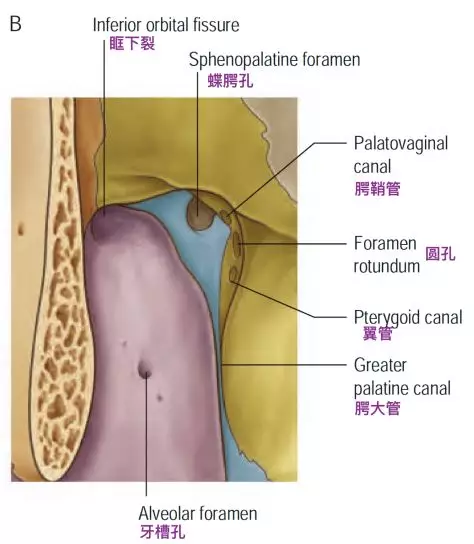

这三个孔隙的向下方穿过颅底后的开口位置是不同的。卵圆孔和棘孔均向下开口于颅底底面,而圆孔向前外侧,开口于颅骨外表面的深部间隙翼腭窝。翼腭窝后壁上的两个开口,分别是圆孔和翼管。翼管内走行翼管神经和翼管动脉。

圆孔连接中颅窝底和翼腭窝,而翼管连接翼腭窝和破裂孔。圆孔位于翼管的上、外侧。

翼腭窝前内侧观示意图,注意圆孔和翼管的位置(Standring, 2016)。

翼管和颅底,下面观(Osawa 2009)。切除翼突,显露翼管神经通过翼管,加入翼腭神经节和上颌神经。翼管神经经过破裂孔前外侧上表面。蝶窦位于翼管的内侧和外侧,邻近卵圆孔和V2。